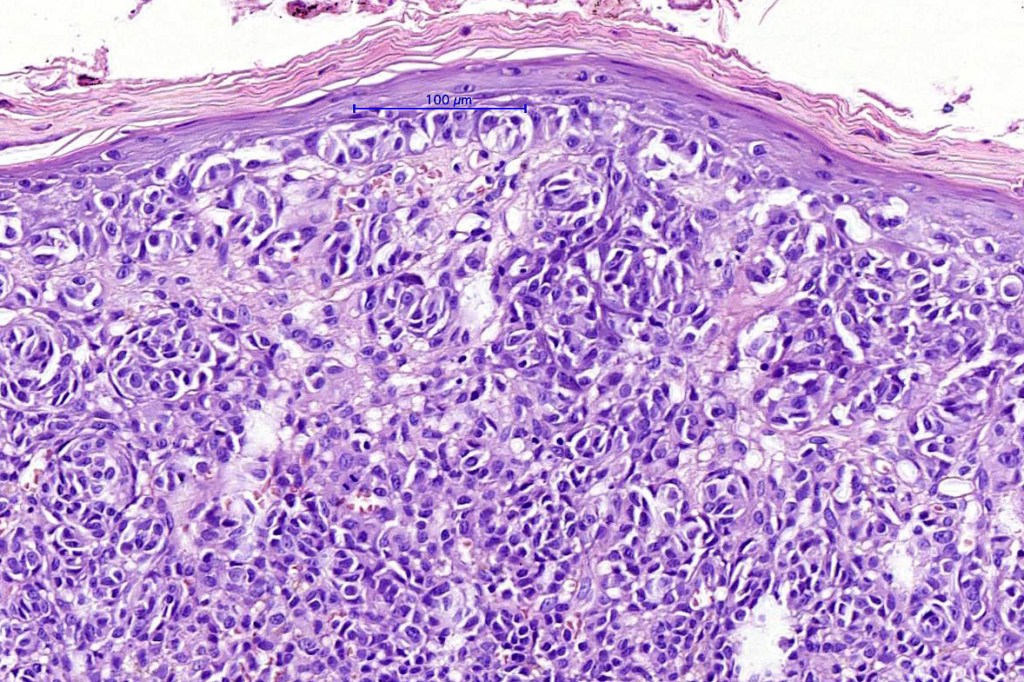

•Mimics type-A cells, (lesions which mimic type B nevus cells are often classified as small cell melanoma, this is important as the differential diagnosis is very different- see separate blog)

•Subtle or not so subtle impaired maturation with depth (sometimes this is evident at scanning magnification)

•Subtle nucleolar prominence

•Subtle pleomorphism

•Mitoses invariable including often in the deep aspect